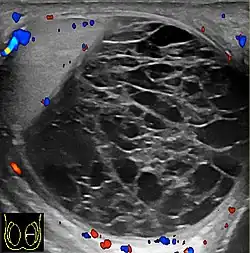

Scrotal ultrasonography of a hematocele, a couple of weeks after appearance, as a fluid volume with multiple thick septations. The hematocele displays no blood flow on Doppler ultrasonography. A pyocele has a similar appearance, but was excluded by lack of inflammation.